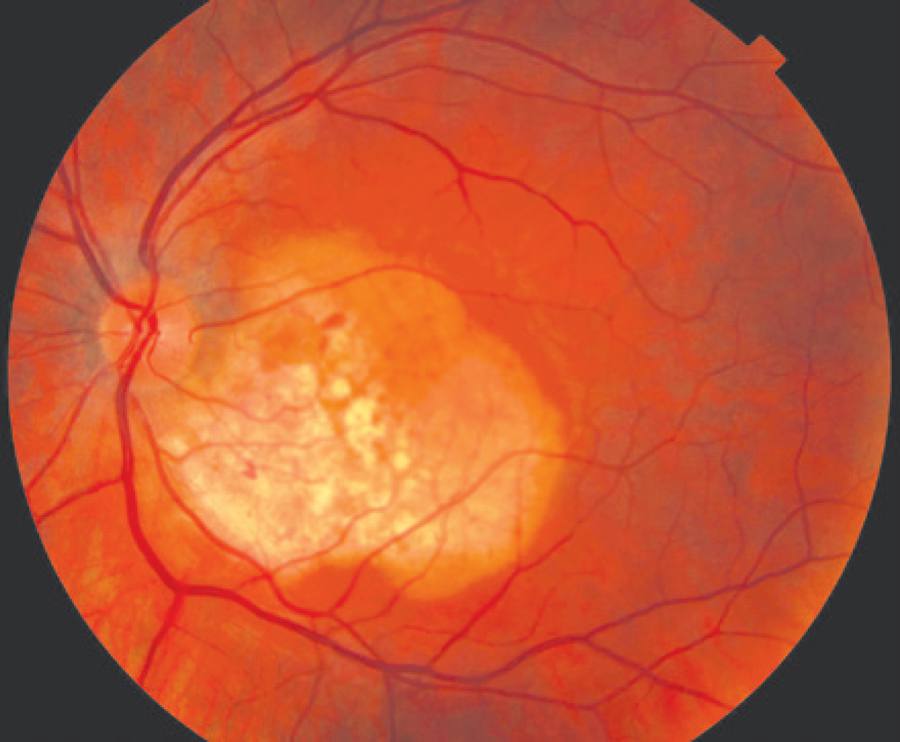

A 24-year-old Caucasian male experienced a sudden vision loss in his left eye. His best corrected visual acuity was 20/20 in the right eye and 20/40 in the left eye. His anterior segment examination was normal. The fundus examination revealed a choroidal osteoma involving the macular area and upper temporal vascular arcade with subretinal hemorrhage and subretinal fluid in the fovea (Figure 1).

In both cases, the lesion had a yellow-white coloration with finger-like projections and pigmentary changes in the overlying RPE. The lesions were minimally elevated (<1.2 mm) and hyperreflective on ultrasonography, and both cases showed small areas of decalcification. Fluorescein angiography showed early patchy hyperfluorescence and late staining, and the choroidal neovascular membranes were found in the decalcified areas in both cases. We observed an angiographic leakage in the area of the membrane. On SD-OCT, the neovascular membrane was superior to the fovea and nasal to the fovea in cases 1 and 2, respectively; both cases had the presence of subretinal fluid.